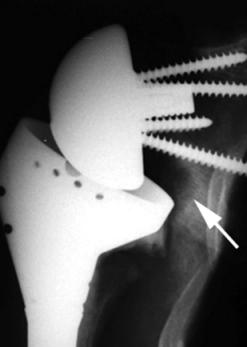

위의 사진과 같이 기존의 인공관절은 humerus 의 골두를 제거하고 glenoid 모습과 비슷하게 작동하는 원리로 인공관절이 되었으나 최근에는 humerus head 의 medialization 효과와 deltoid muscle lever arm의 증가로 더 효과가 있는 reverse shoulder arthroplasty 가 많이 시행되고 있습니다. 1990년대부터 수술을 시작했으니 30년 정도 지난 수술법입니다.

대신 반대로 상완골의 움직이면서 glenoid의 하방부를 notching 하는 부작용이 쉽게 생길 수 있습니다. 이를 scapular notching 이라고 합니다. base plate를 좀더 lateral inferior 하게 삽입하면 이를 예방할 수 있습니다. 또한 glenosphere 크기를 늘리고 lateral offset을 늘리는 방법도 있습니다.